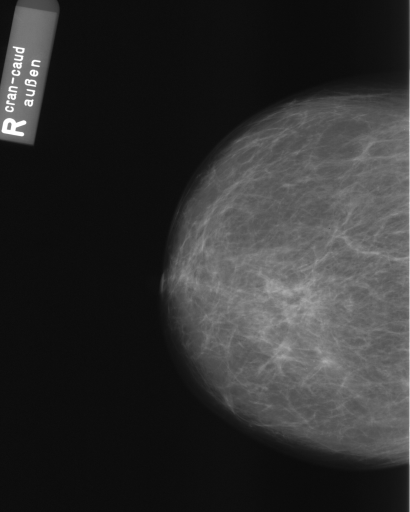

In this series of experiments, we randomly selected three categories from IRMA dataset (namely, breast, foot and lung), and for each category we choose 5 random images from that class (Figures 5, 6 and 7 show these images). When we find “4 out of 180” (4/180) and “8 out of 180” (8/180) projections via micro-DE (tasks that cannot be performed via brute-force), then the question is what can we say about the reconstruction error, in terms of correlation between original and reconstructed images, when we compare evolutionary approximation with the case that we can manage via exhaustive search, namely “4 out of 16” (4/16)? Can micro-DE reach at least the same correlation (similarity) as the brute-force case in lower dimensions? If yes, we may have more confidence in using micro-DE in practice where we cannot apply brute force for benchmarking or direct use, especially for higher dimensions (i.e., the number of projections).

For finding optimal projections based on micro-DE (4 out of 180), we set the parameters of micro-DE to be NFC, , , , and we run each experiment 30 times. For optimal projections based on micro-DE (8 out of 180), we set NFC, , , , and we run each experiment 30 times. The results are presented in Tables 2, 3 and 4. In all cases, micro-DE (MDE) with 4/180 reaches the same correlations as brute force (BF) for 4/16. Of course, MDE finds different projections as it is searching the entire search space of . However, that the same level of reconstruction accuracy can be achieved establishes the reliability of MDE as a practical solution that may even produce a higher-level of uniqueness for Radon barcodes as 4 projections are selected among all 180 angles (the increased uniqueness needs to be verified by applying the Radon barcodes for image retrieval). On the other hand, MDE for 8/180 clearly increases the correlation with statistical significance. This is very encouraging as we can generate more expressive Radon barcodes using a higher number of projections.

| image | BF (4/16) | MDE (4/180) | MDE (8/180) | |||

|---|---|---|---|---|---|---|

| b1 | [22,67,123,157] | 0.83 | [30,50,120,160] | 0.83 | [70,130,30,120,100,150,170,50] | 0.89 |

| b2 | [33,67,123,169] | 0.83 | [30,70,120,160] | 0.83 | [170,140,150,60,40,80,20,110] | 0.89 |

| b3 | [22,67,123,157] | 0.81 | [30,50,120,160] | 0.81 | [150,170,10,70,40,130,110,50] | 0.85 |

| b4 | [11,56,146,169] | 0.81 | [20,60,120,160] | 0.80 | [160,20,120,170,40,30,130,70] | 0.86 |

| b5 | [11,56,112,157] | 0.81 | [20,60,120,160] | 0.81 | [80,20,120,60,160,90,10,140] | 0.86 |